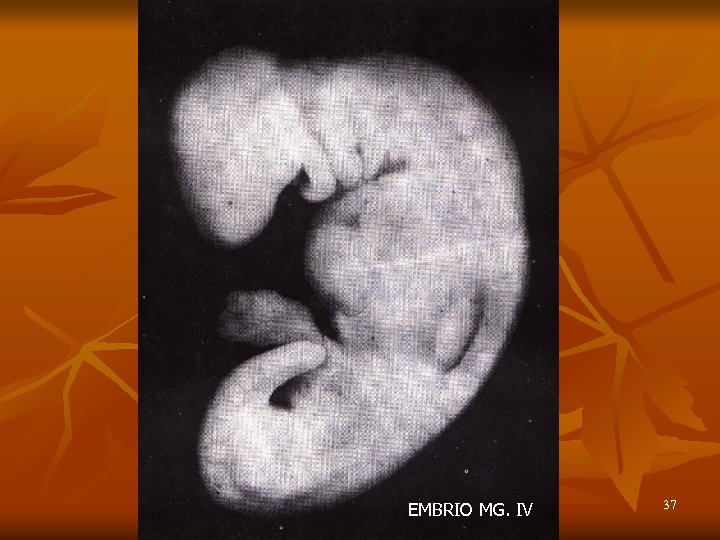

EMBRIO MG. IV 37